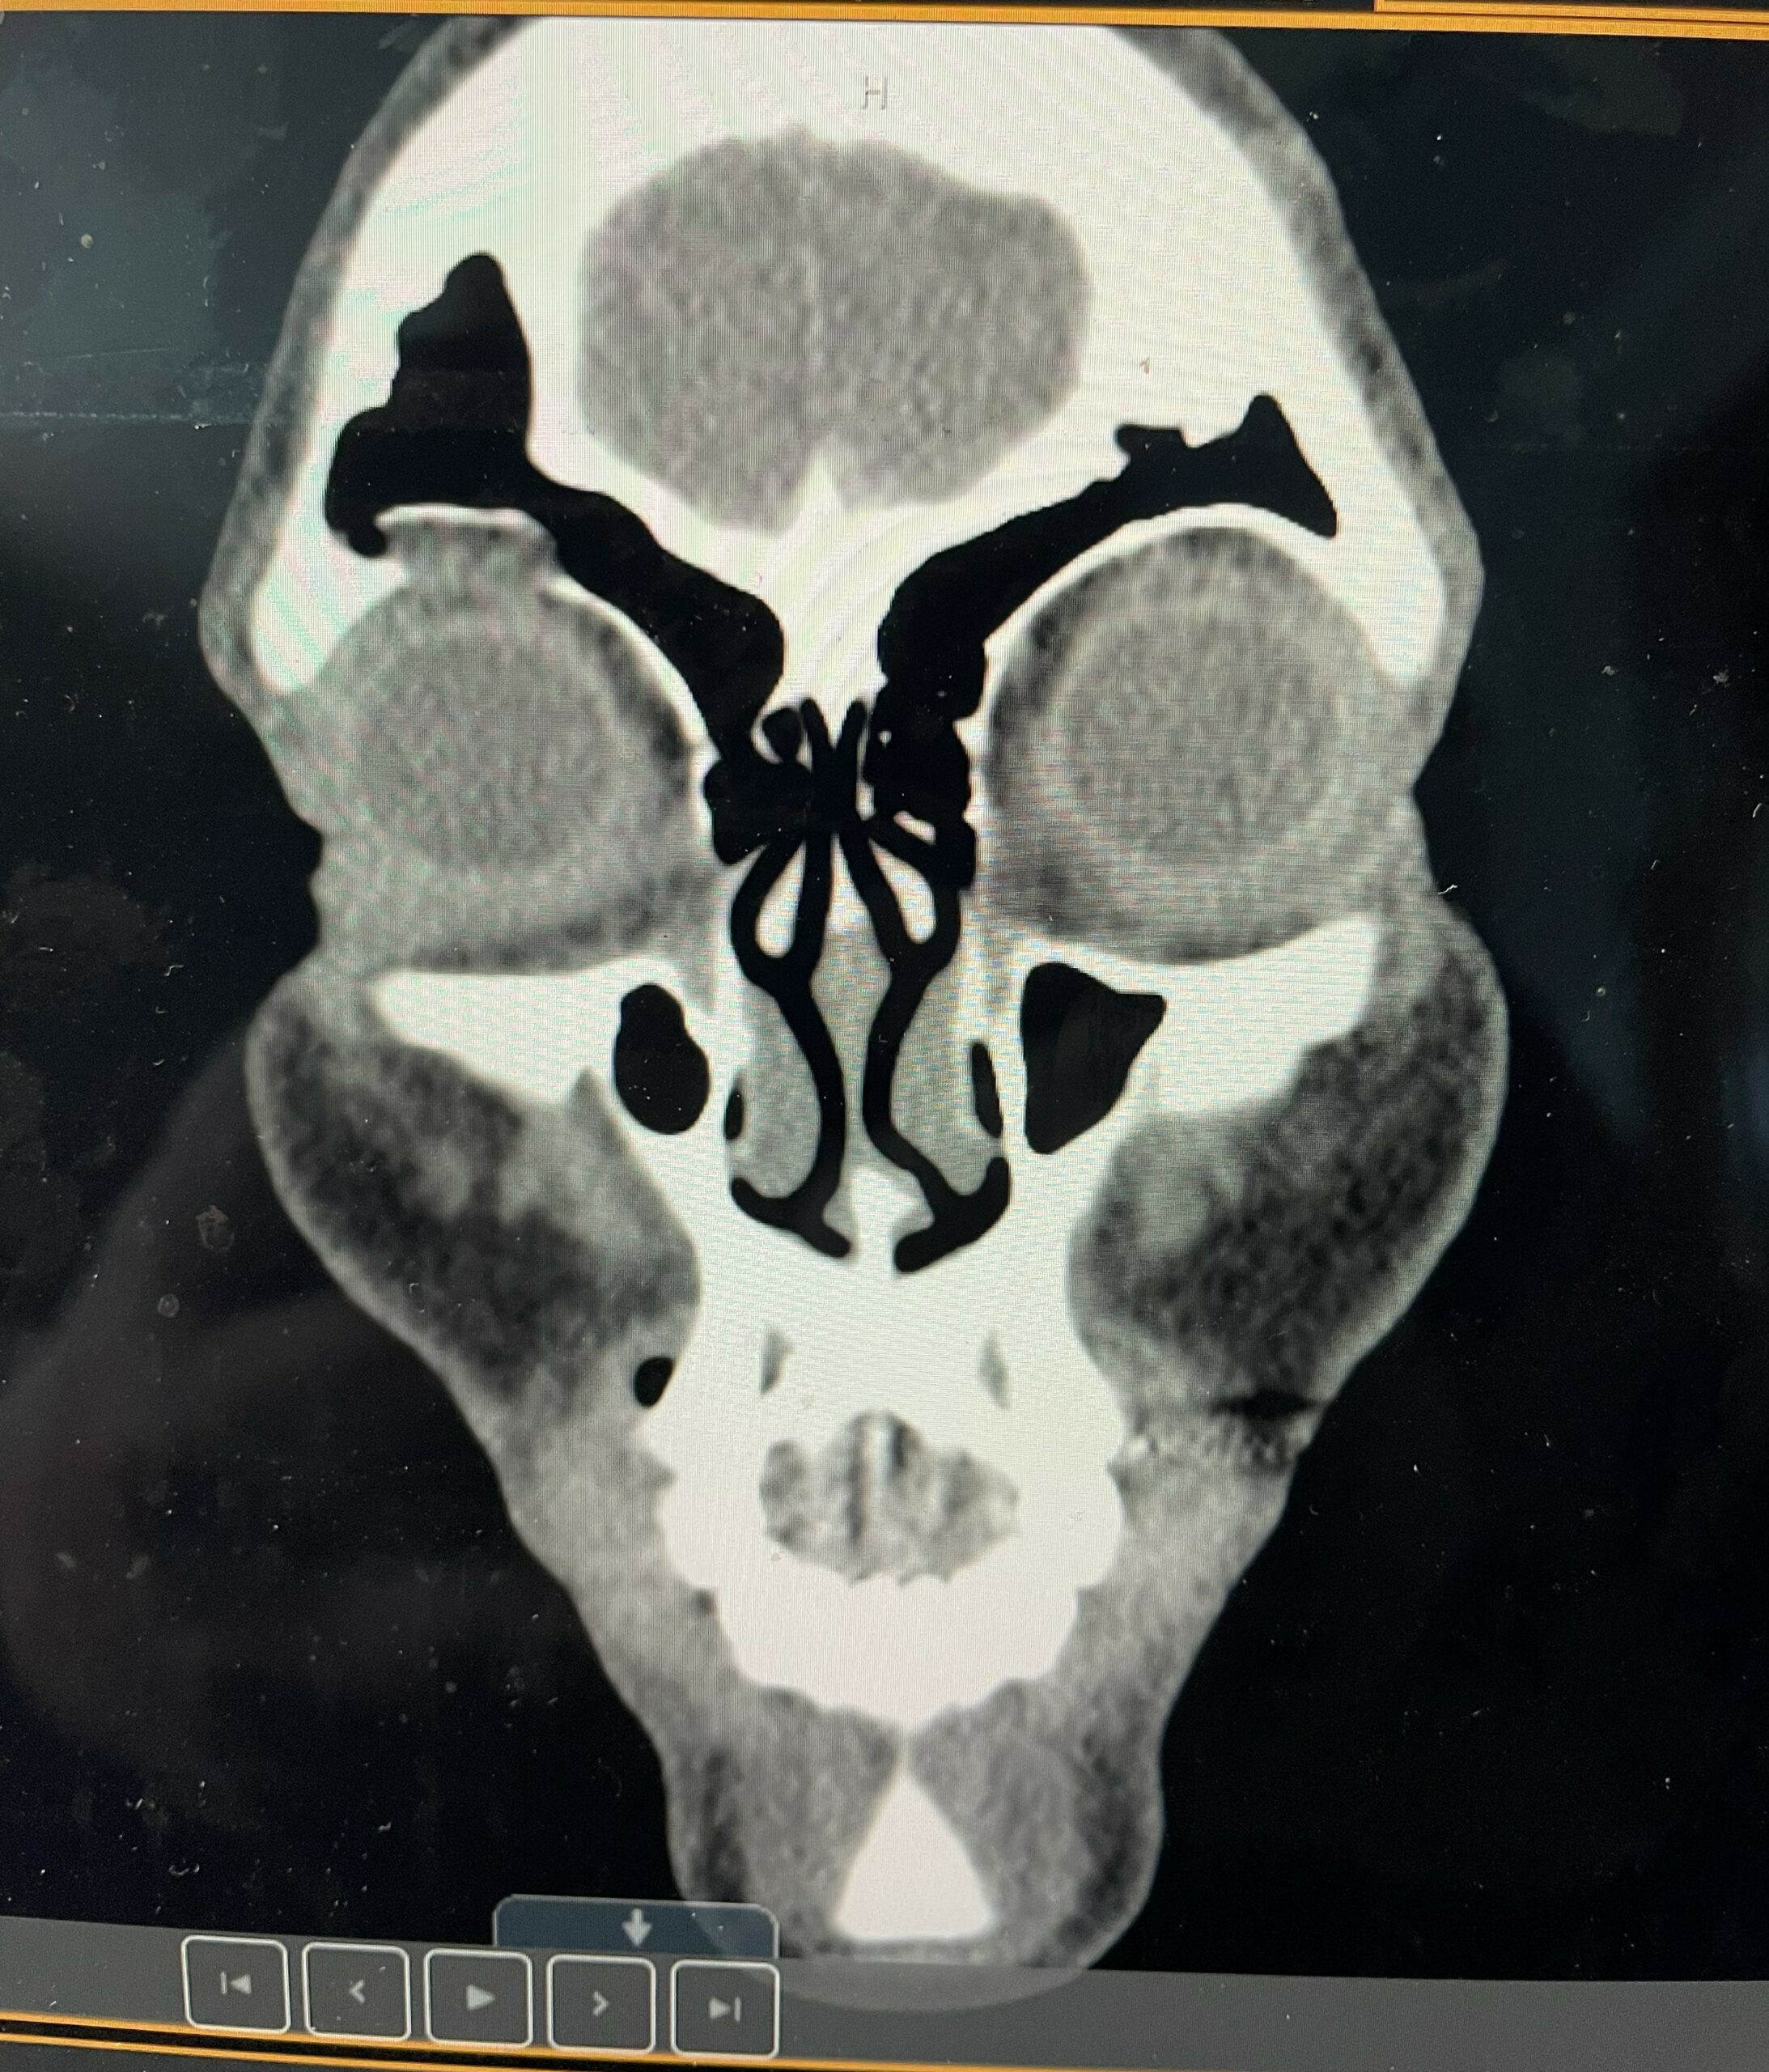

Following the brutal attack, it has been revealed that The Nightmare has suffered a fractured right orbital socket, which will put Ripley out of action for an undisclosed amount of time.

“[Rhea has] got a fractured orbital bone,” Dave Meltzer said on “Wrestling Observer Radio” recently. “So the injury they announced is pretty much legit. It happened last week…Probably the last TV thing because she didn’t work any house shows.”